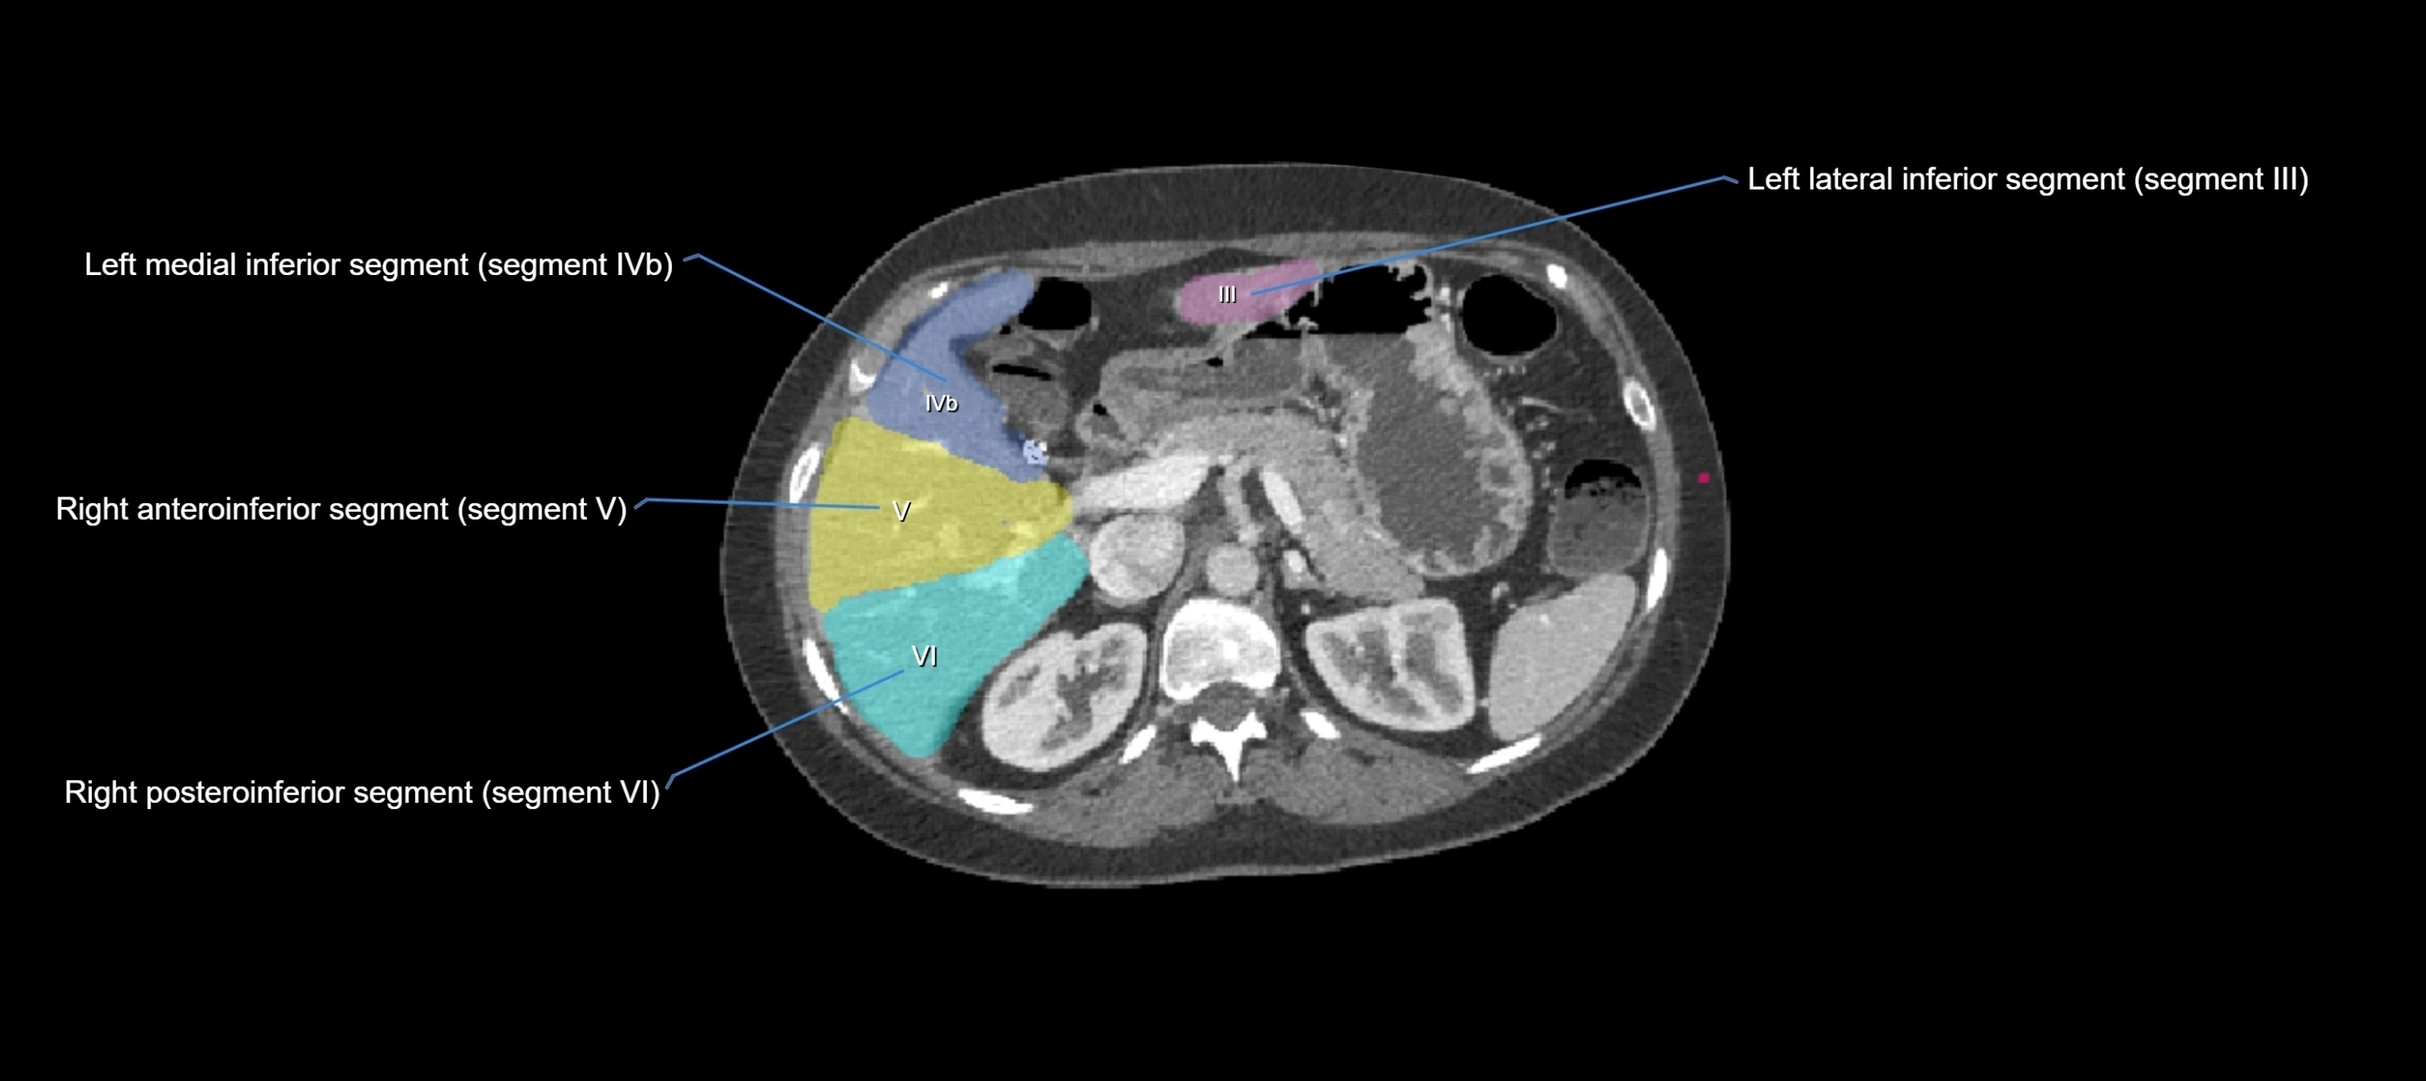

CT Appearance

CT Pre-Contrast:

• Caudate lobe appears as a soft-tissue density, isodense to the rest of the liver

• Enlargement may be appreciated in cirrhosis or Budd–Chiari syndrome

CT Post-Contrast:

• Homogeneous enhancement in the portal venous phase, similar to rest of liver

• Independent venous drainage into the IVC may be visualized

• Lesions follow characteristic CT enhancement patterns (HCC: arterial hyperenhancement with washout; hemangiomas: peripheral nodular enhancement with centripetal fill-in)

CT Venous Phase (functional significance):

• Caudate lobe often enhances relatively more than other lobes in Budd–Chiari syndrome, due to preserved venous outflow

CT Image

image